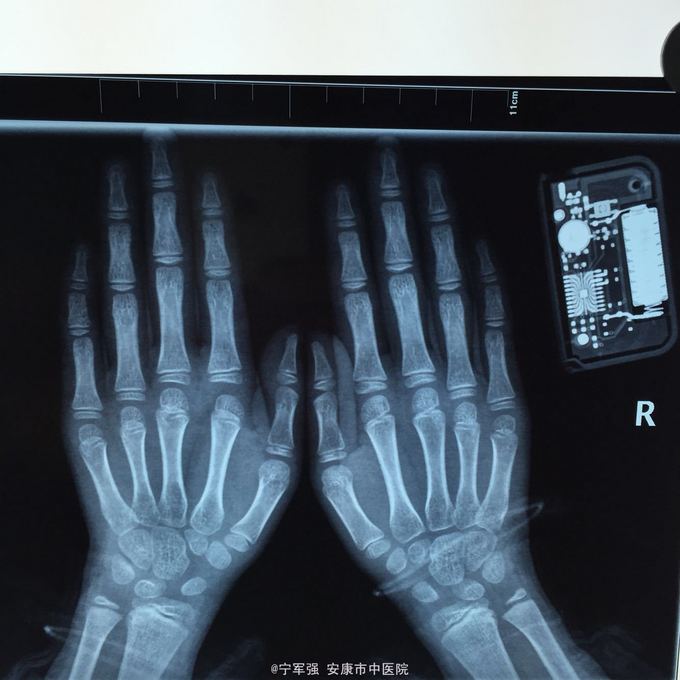

患者8岁,女 扭伤致左手食指肿痛活动受限2小时

患者一般情况良好,左手第二掌指关节处肿胀,弹性固定于伸直位,活动受限,压痛明显,循环尚可

诊断:左手第二掌指关节脱位 处理,予以手法复位失败!考虑关节囊坎顿,阻止复位 予以局麻小切口探查证实,复位脱位,修补关节囊

指骨夹板固定,复查x线显示复位良好 随诊